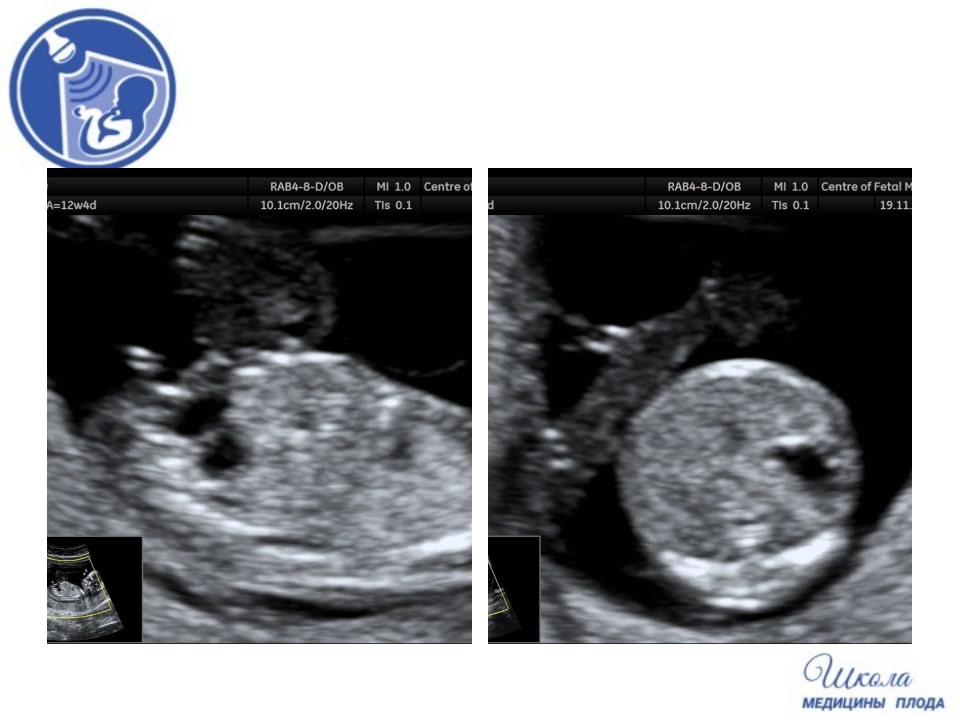

Вопрос 4

Проанализируйте УЗ-снимки, полученные в ходе первого скринингового УЗИ.

Пациентка хочет сдать НИПТ на 5 самых частых хромосомных болезней (трисомия 21,18, 13 и аномалии половых хромосом). Что Вы ей порекомендуете?